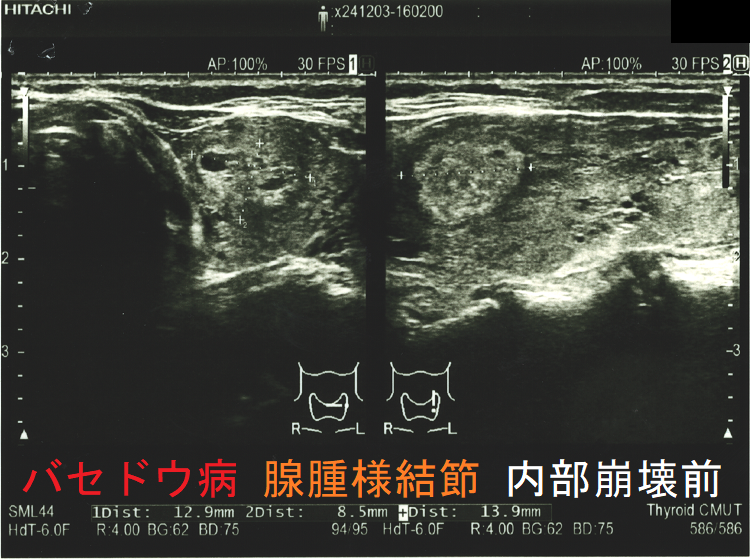

穿刺細胞診後内部融解

ケース①

ケース②